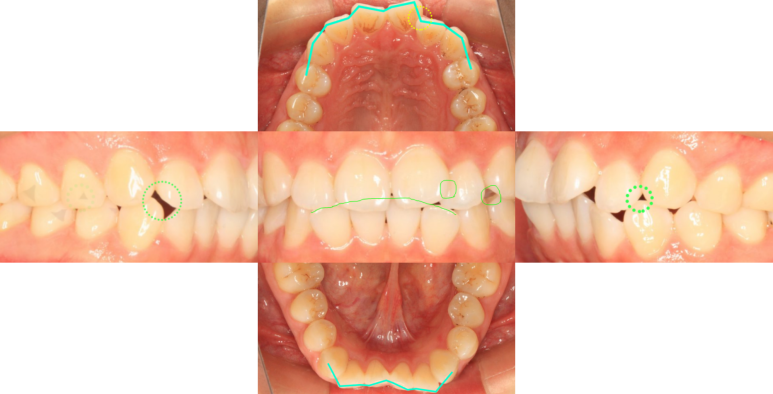

서울리멤버치과의원의 네이버 블로그 원문을 보존한 아카이브 페이지입니다. 교정케이스 모음집 카테고리의 삐뚤어진 앞니 치료 전 글을 통해 병원의 한국어 정보 제공 방식과 진료 관련 안내 톤을 확인할 수 있습니다.

교정케이스 모음집